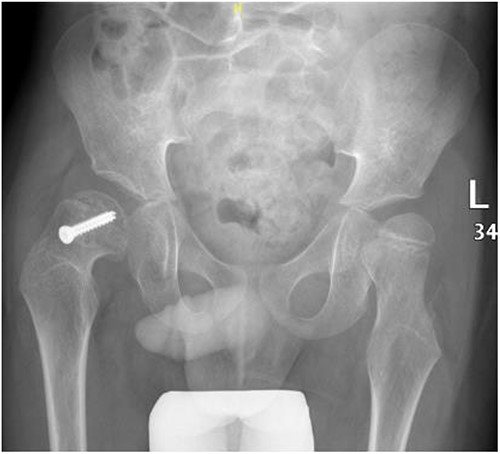

A 5-year-old independent ambulatory Middle Eastern boy with CP who was born preterm and developed grade III intraventricular haemorrhage and periventricular leucomalacia and was on AEDs, including valproic acid (VPA) and levetiracetam (LEV), for >3 years and was controlled over the last year (no history of seizure attack) presented to the emergency room (ER) with right hip pain and inability to bear weight for 4 weeks; the patient had no history of fever or trauma. Physical examination shows a thin, the weight is 12 kg, the height is 101 cm, vital signs within the normal range, tenderness over the right hip, and external rotation of the right hip, with restricted hip mobility. A radiological study was performed ~3 months before the patient presented to the ER for follow-up examination of a left hip coxa valgus deformity with no apparent abnormalities in the right hip (Fig. 1). Initial imaging studies conducted in the ER showed an anterior–posterior view of the pelvic radiograph, revealing Klein’s line [13] not intersecting the capital femoral epiphysis (Fig. 2), and frog-leg lateral view radiograph of the right hip (Fig. 3) confirmed SCFE and Southwick’s slip angle [13] of ~50° (moderate). Laboratory findings were clear for endocrine and renal diseases or infection, except for low vitamin D (total 25-OH Vitamin D: 43.4 nmol/L), suggesting vitamin D insufficiency. The diagnosis was confirmed with clinical and radiological studies as right-sided unstable SCFE requiring surgery. Surgical intervention was performed with percutaneous in situ fixation using a single fully threaded 4.5-mm cannulated screw (Fig. 4). Postsurgical rehabilitation included non-weight-bearing right lower extremities for 6 weeks. Regular follow-up with serial radiology studies showed stable fixation with no migration of screw or further slippage at 6 weeks (Fig. 5) and 3 (Fig. 6), 15 (Fig. 7), and 36 months (Fig. 8). During follow-up, a painless range of motion in the right hip was observed, with full weight-bearing and resumption of his usual activities with no complaints.

Pelvic anterior–posterior radiograph showing SCFE in the right hip, with Klein’s line not intersecting the capital femoral epiphysis